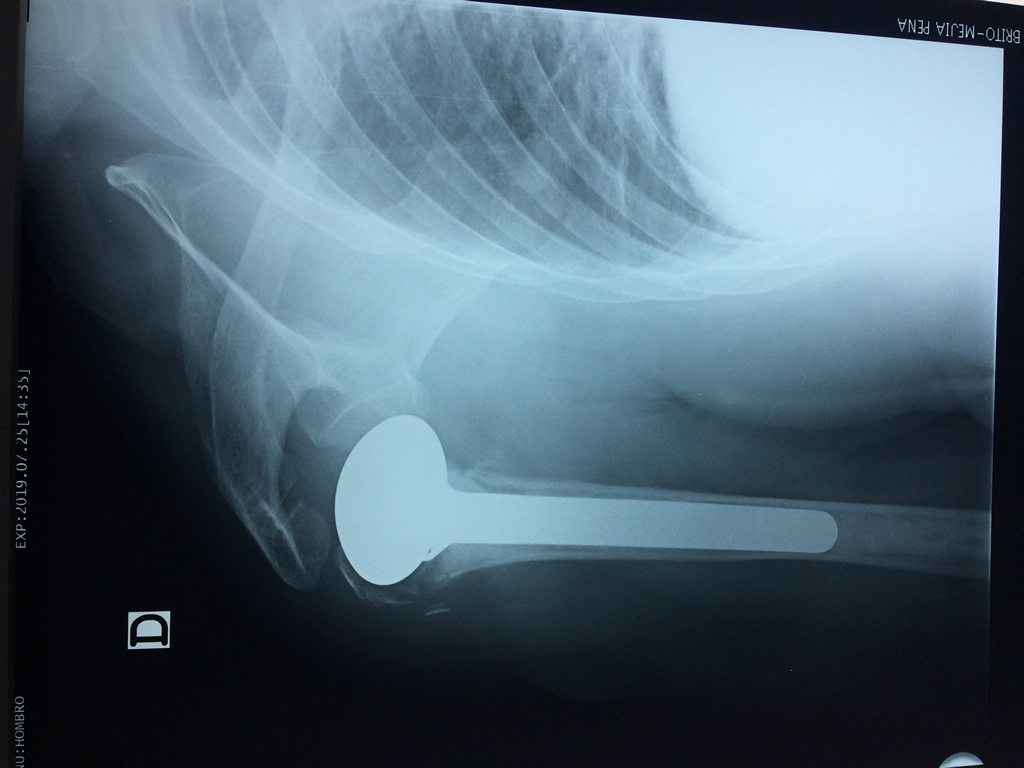

En anatomía humana, el hombro es la parte del cuerpo donde se une el brazo con el tronco. Está formado por la conjunción de los extremos de tres huesos: la clavícula, la escápula y el húmero; así como por músculos, ligamentos y tendones.

La principal articulación del hombro es la que une la cabeza del húmero con la escápula, recibe el nombre de articulación escapulohumeral y presenta dos superficies articulares, una de ellas corresponde a la cabeza del humero que tiene forma semiesférica y la otra es la cavidad glenoidea de la escápula, estas superficies están recubiertos por cartílago que permiten un movimiento suave e indoloro.

Exteriormente una envoltura de tejido blando circunda el conjunto, es la llamada cápsula articular que está reforzada por varios ligamentos que le dan estabilidad e impiden que los huesos se desplacen más allá de sus límites fisiológicos. Un conjunto de músculos y sus tendones se unen a las superficies de los huesos y hacen posible la movilidad de la articulación, entre ellos es muy importante el manguito rotador formado por cuatro músculos que proporcionan movilidad y estabilidad al hombro.